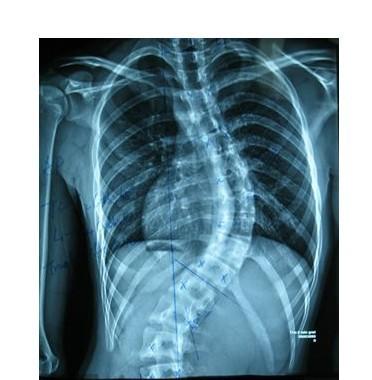

强直性脊柱炎

QZ16030094 姓名:陈先生 性别:男 年龄:32岁

- 病情

AS ①晚期 ②重度 病史:5年+

- 治疗

治疗后骶髂关节疼痛消失,腰椎前屈、背伸侧弯活动自如,膝关节无压痛感,复查血沉、C反应蛋白、等各项检查均已达到临床康复的标准。